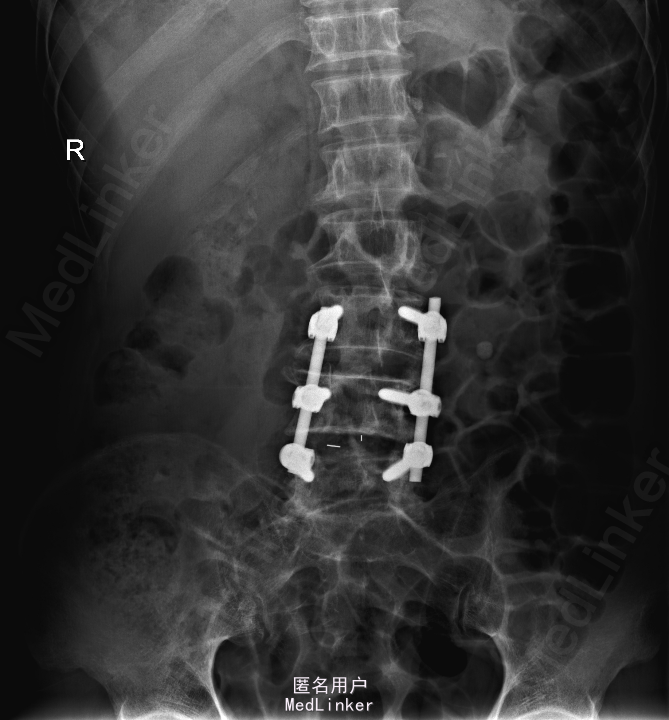

查体:左侧小腿外侧、足背感觉减退,右侧正常,双侧屈髋、伸膝、踝背伸肌肌力5级,左侧踇背伸、跖屈肌肌力4级,右侧踇背伸、跖屈肌肌力4-5级,双侧巴氏征阴性,直腿抬高试验左侧30°阳性,右侧阴性。 辅助检查: X-ray:腰椎退行性变,腰椎节段性性不稳 MR:腰椎间盘突出,腰3/4,4/5,腰4/5节段明显

诊断:腰椎椎管狭窄 处理: 1、完善相关辅助检查,明确诊断,有无手术指证; 2、完善手术评估,有无手术禁忌,手术风险及并发症; 3、在全麻下行腰椎后路减压,腰3/4左侧椎板减压,腰4/5椎间Cage植骨融合内固定术

随访 术后患者下肢麻木感觉较前好转,左侧踝背伸、跖屈肌力4级+,左侧肢体抬高试验阴性。术后MR检查减压彻底 讨论:1、腰椎椎管狭窄手术指证的把握,腰椎后路手术,腰椎椎间融合与椎板减压的选择? 2、术中探查如无明显间盘突出,以椎管骨性狭窄为主,可行腰椎后路椎板减压为主。